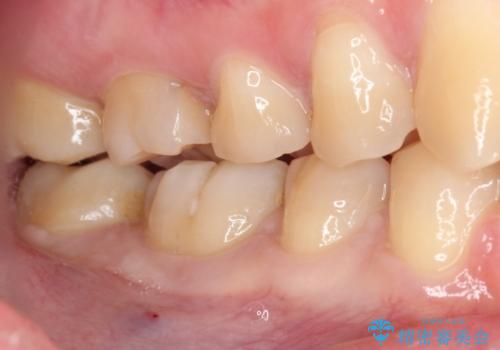

- 矯正治療後に目立つ銀歯を白くしたいとのことで来院された患者様です。

右下の銀の詰め物は、外してむし歯を除去した後、セラミックインレーにて修復することとしました。

左上の銀歯は、銀歯の下に金属の土台が入っているため、その土台を除去し、ファイバーコアにやり替えて、オールセラミッククラウンにて補綴することとしました。

適合の良いセラミック治療は、むし歯再発のリスクが低いです。

目立つ銀歯がなくなり、患者様は大変満足されました。